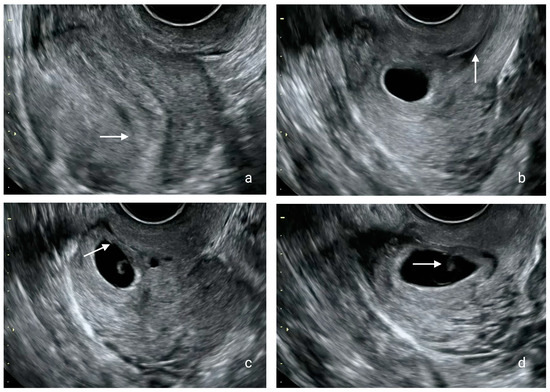

2. Detailed Case Description